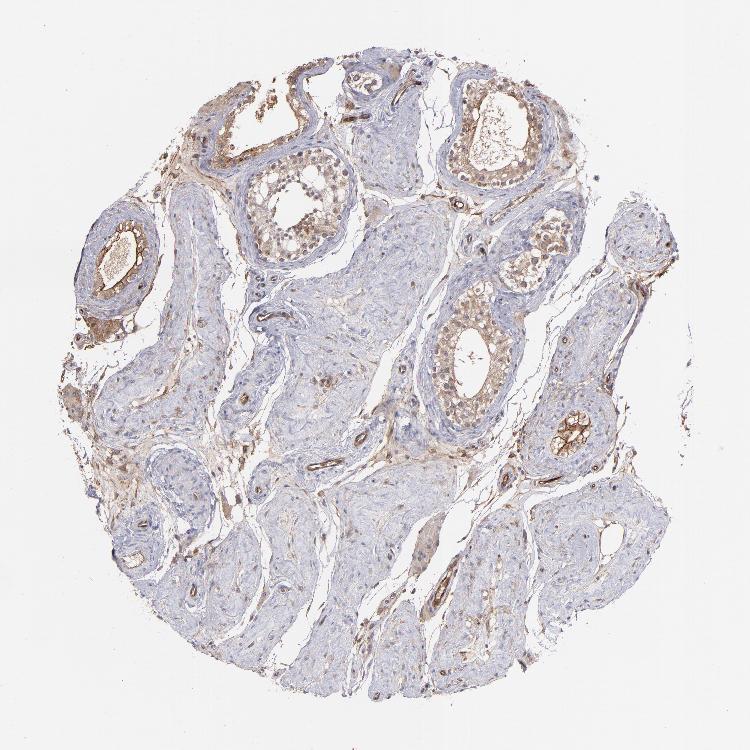

Antibody staining in the annotated cell types in the current human tissue is reported as not detected, low, medium, or high. This score is based on the staining intensity and fraction of stained cells.

Information about each individual sample is listed below, including gender, age, a tissue section image and estimated fractions of cell types. pTPM (transcripts per million) values give a quantification of the gene abundance which is comparable between different genes and samples.